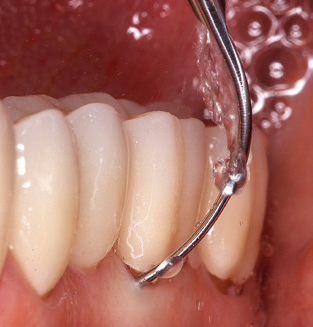

Unerlässlich für die UPT implantat­ prothetisch versorgter Patienten sind natürlich Arbeitsspitzen für die Reini­gung von Implantatoberflächen. Der Implantatreinigungsaufsatz des hier verwendeten Systems zeichnet sich dabei durch eine spitz zulaufende sechskantige konische Form aus. Dieses Design erlaubt ein leichtes atraumatisches Eindringen in die periimplantäre Tasche und zeigt eine gute Reinigungsleistung (Abb. 7).

Abb. 4: Für das Sondieren an dentalen Implantaten sind biegsame, millimeterskalierte Sonden empfehlenswert (z.B. Colorvue Kit PCV11KIT6, Hu-Friedy). – Abb. 5a und b: Eine gerade Arbeitsspitze (1P, W&H Dentalwerk Bürmoos GmbH) ist universell für die Instrumentierung natürlicher Zähne geeignet. – Abb. 6: Für die Bearbeitung schwer zugänglicher Bereiche der Zahn- und Wurzeloberflächen (z.B. Furkationen) bieten sich gebogene Arbeitsspitzen (3Pr/3Pl, W&H Dentalwerk Bürmoos GmbH) an. – Abb. 7: Die spitz zulaufende sechseckige Implantatreinigungsspitze (1I, W&H Dentalwerk Bürmoos GmbH) ermöglicht eine atraumatische und effiziente Reinigung der Kronen- und Abutmentoberflächen. – Abb. 8: Für die manuelle Instrumentierung der Implantatoberflächen sind Titan- oder Carbonküretten geeignet.